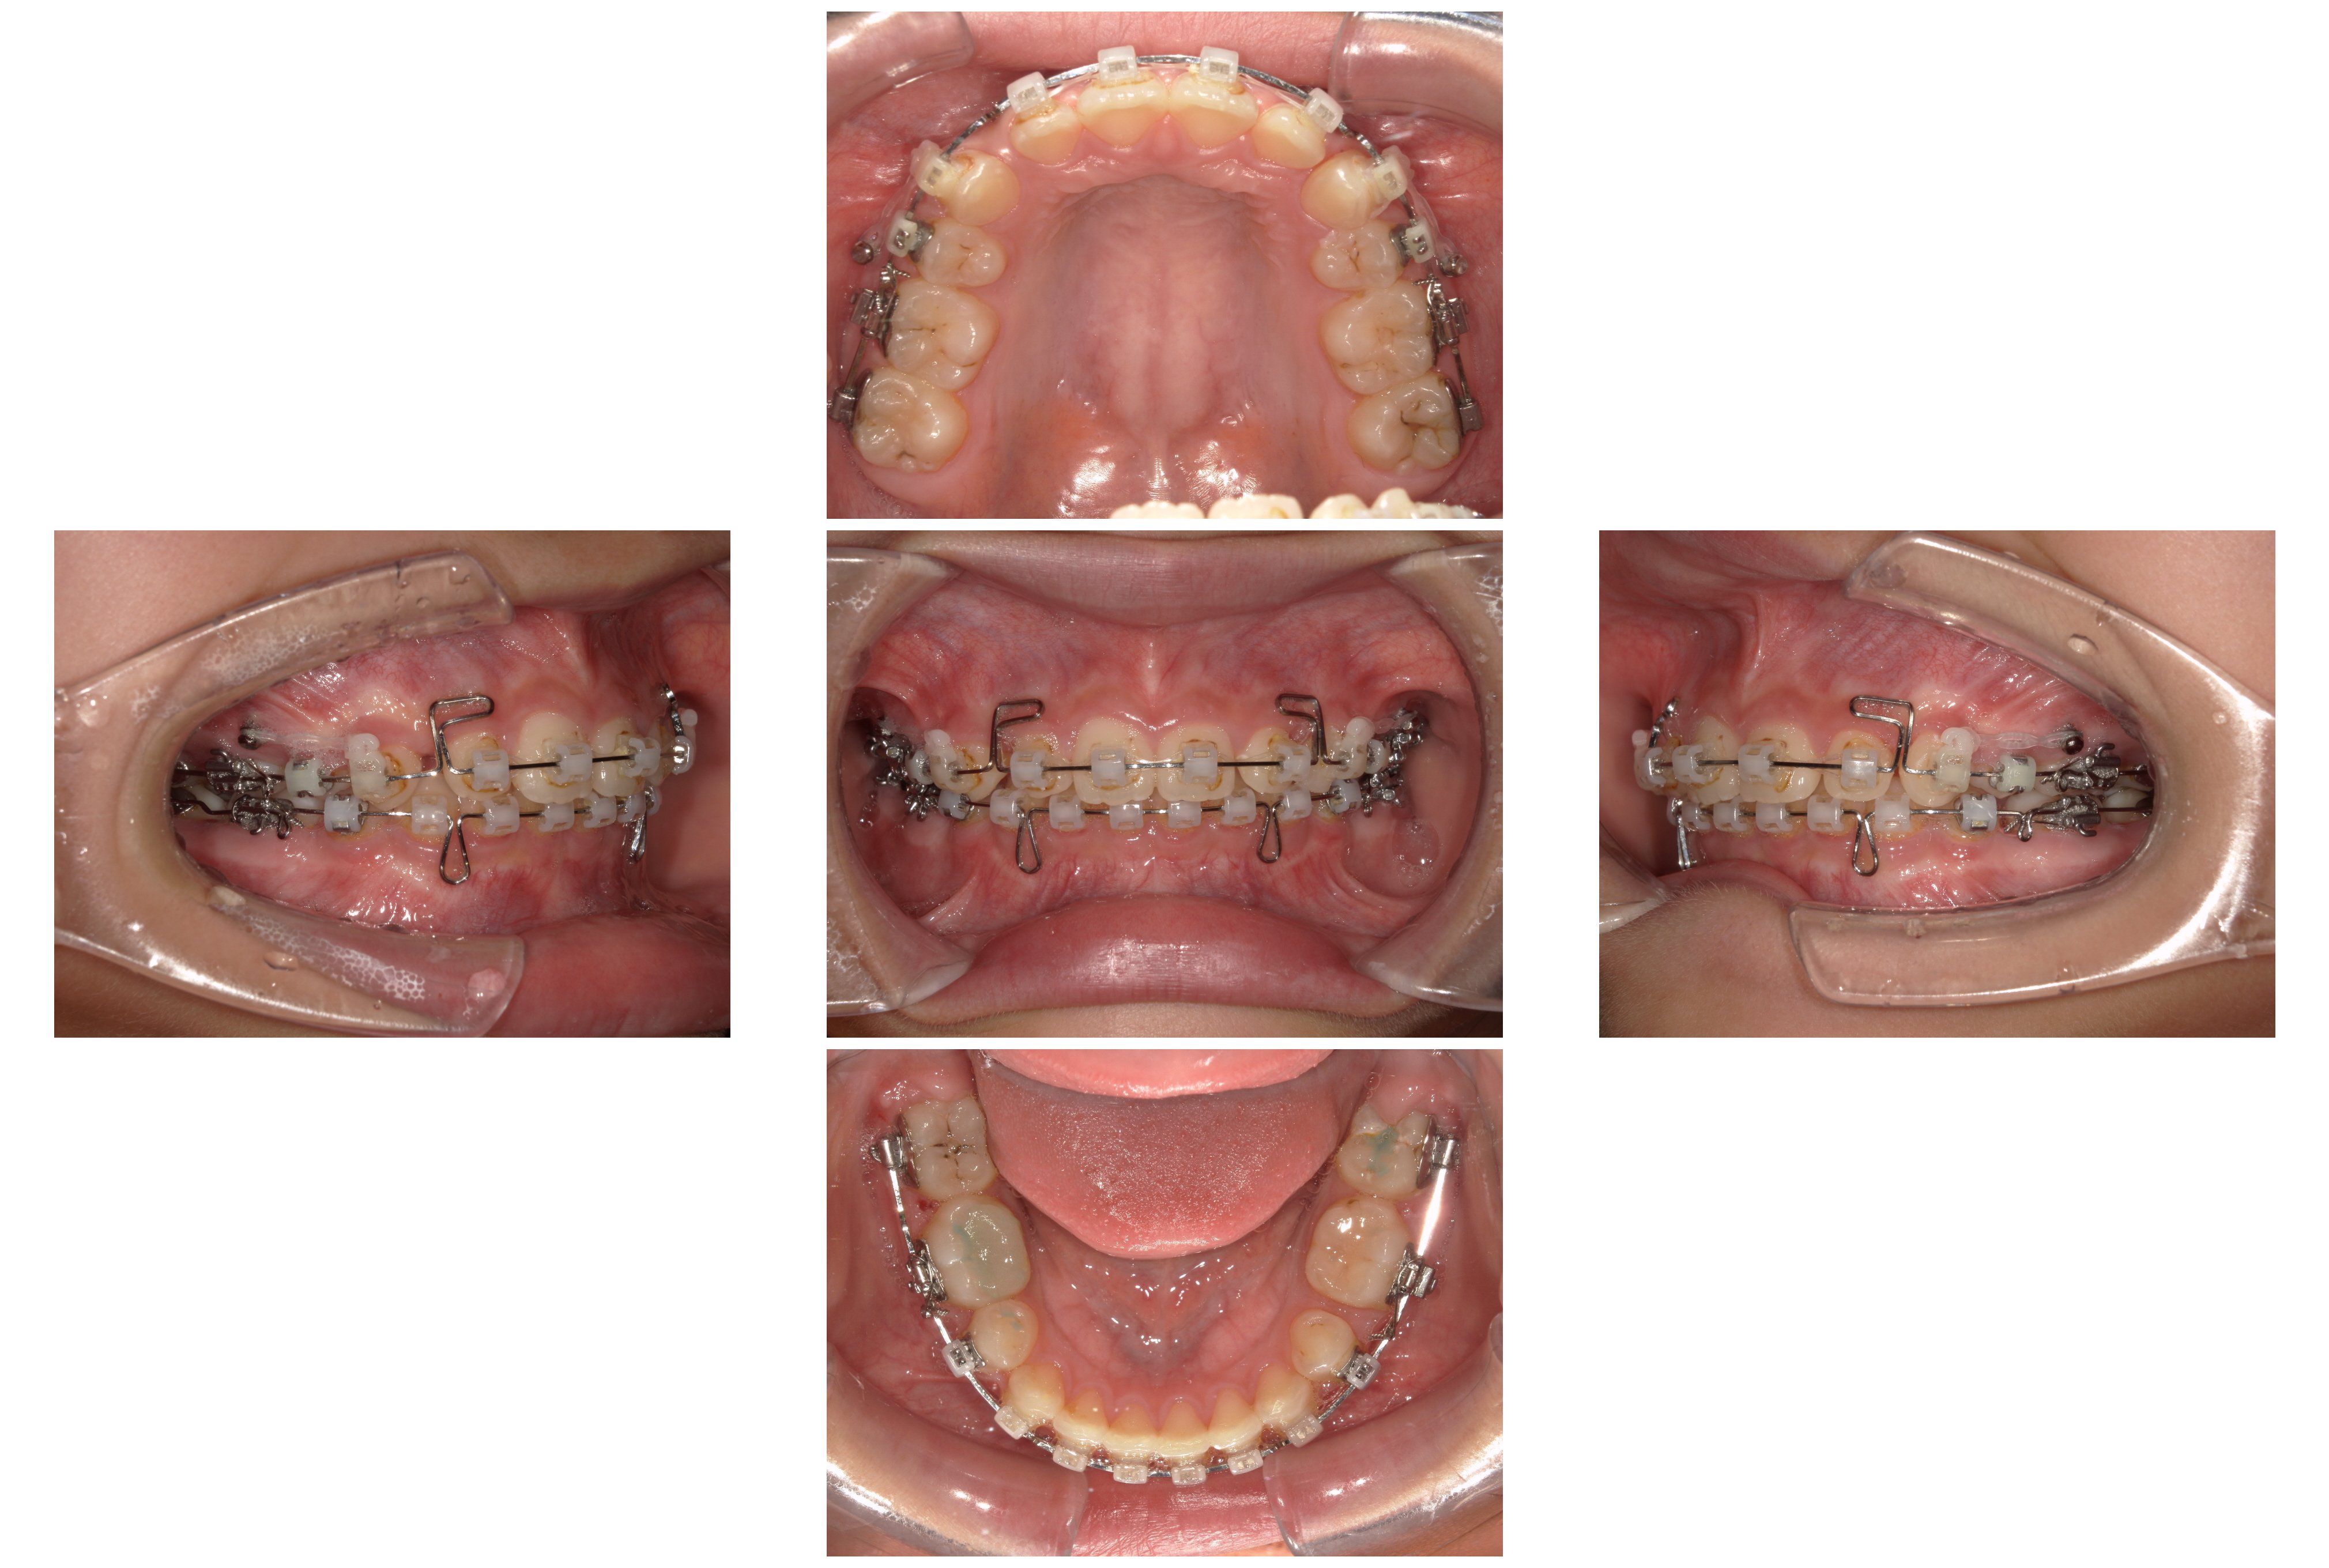

▼2023年4月

②装置装着8か月後:レジンマウントによる挙上

さらに下顎の奥歯に「レジンマウント(プラスチックの盛り物)」を装着し、咬み合わせの高さ(咬合高径)を強制的に確保しました。これにより、歯が動く際の邪魔な干渉を取り除きます。